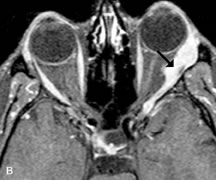

MRI is an excellent modality for demonstrating enlargement of the cavernous sinus and dilation of the superior ophthalmic vein in patients with high-flow carotid-cavernous fistulas (Fig. 14).37MRA may be helpful in the evaluation of the venous outflow pattern. The rapidly flowing blood in these vascular structures carries the excited protons out of the section before they can be imaged, resulting in their dark appearance.5 In low-flow dural arteriovenous malformations, MRA may help define the arterial feeding vessels.45

Fig. 14. Patient with Ehlers-Danlos syndrome who presented with abrupt onset of severe proptosis. A-C. Postcontrast fat-suppressed T1-weighted MR scans demonstrate marked proptosis and engorgement of the extraocular muscles and superior ophthalmic vein (arrows). D. T2-weighted scan through the cavernous sinus demonstrates enlargement and arterialized flow void within the right cavernous sinus (open arrow).